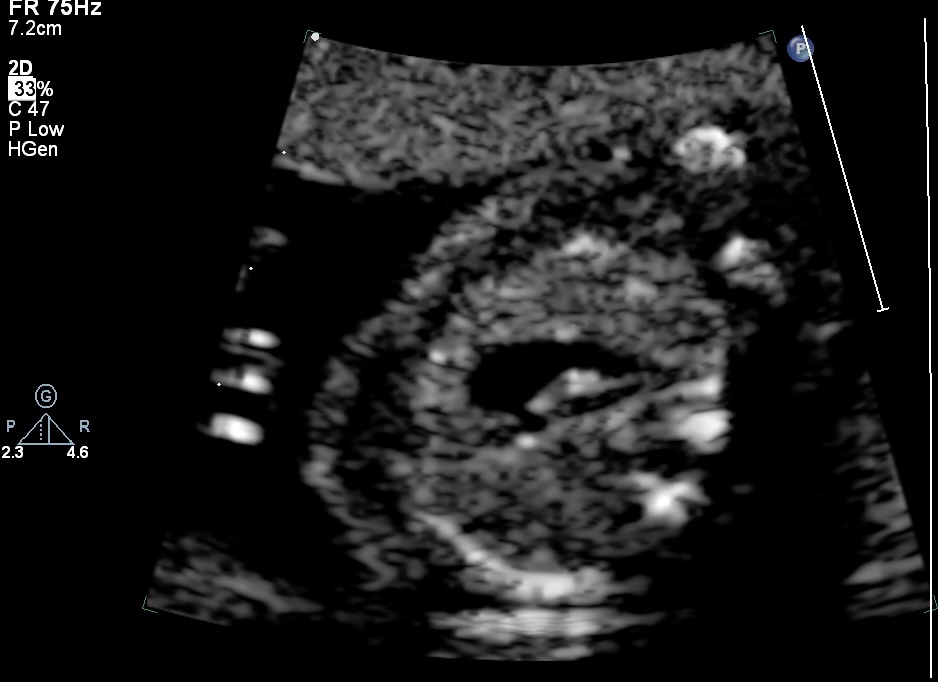

Image: Case of Fetal ToF with Right Aortic Arch with a significantly small pulmonary artery and a small Thymus. Dipicting high-risk features for the likelihood of the post-natal duct dependency and association with 22q11 deletion.